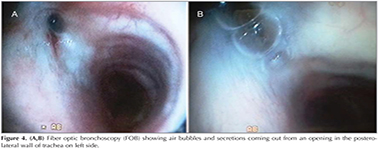

General physical and systemic examination revealed nothing abnormal except fine crepitations in left infra-scapular and infra-axillary region. Laboratory investigations were within normal limits. Pulmonary function test was normal without signs of bronchial obstruction and sputum was negative for acid fast bacilli. Her chest skiagram PA view showed left lower zone infiltrates with air-bronchogram, loss of lung volume on left side and same side shifting of mediastinum, over all finding suggestive of left lower lobe collapse with consolidation (Figure 1). Contrast enhanced chest tomography (CECT) scan of chest showed loss of lung volume on left side with lower lobe cicatricial collapse and consolidation with air-bronchogram while the scanogram revealed a small bud like projection on left para tracheal region, at the level of the thoracic inlet (arrow) (Figure 2A,B). The presence of a narrow stalk connecting the lesion with the posterior wall of the trachea was critical in establishing the diagnosis of a tracheal diverticulum. Furthermore, three-dimensional reconstruction CT ?virtual bronchoscopy confirmed our diagnosis as it showed an orifice of tracheal diverticulum in tracheal wall on left side just below the vocal cord (Figure 3). Fiber optic bronchoscopy (FOB) showed air bubbles and secretions coming out from an opening in the postero-lateral wall of trachea on left side approximate 1 cm below the vocal cords (Figure 4A, B). Further FOB revealed marked narrowing of the left lower lobe bronchus suggestive of cicatricial collapse. The diagnosis of tracheal diverticulum with left lower lobe collapse was made. The barium contrast study performed to look for any esophageal communication, but to fail (Figure 5). Bronchoalveolar lavage taken during FOB, sent for gram stain and pyogenic culture. Patient was referred for surgical management looking at the frequency of symptoms, but she denied for any operative intervention. She was then managed conservatively with antibiotics, mucolytics and vaccinations to reduce the frequency of chest infections and subsequent complication.